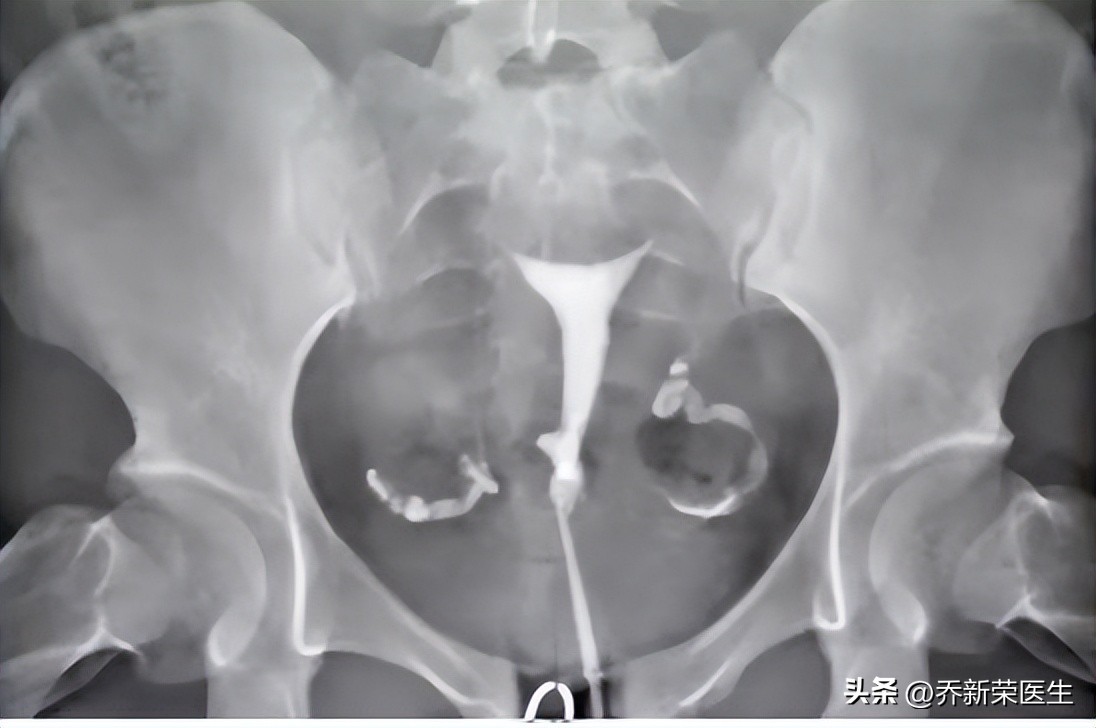

输卵管造影的原理是在X线下可视检查,诊断输卵管功能,判断是否输卵管阻塞的金标准。它可以较为直观地看到输卵管是否通畅或者狭窄以及阻塞部位、初步评估输卵管伞端的基本情况,并根据检查结果制定相应的诊疗方案。